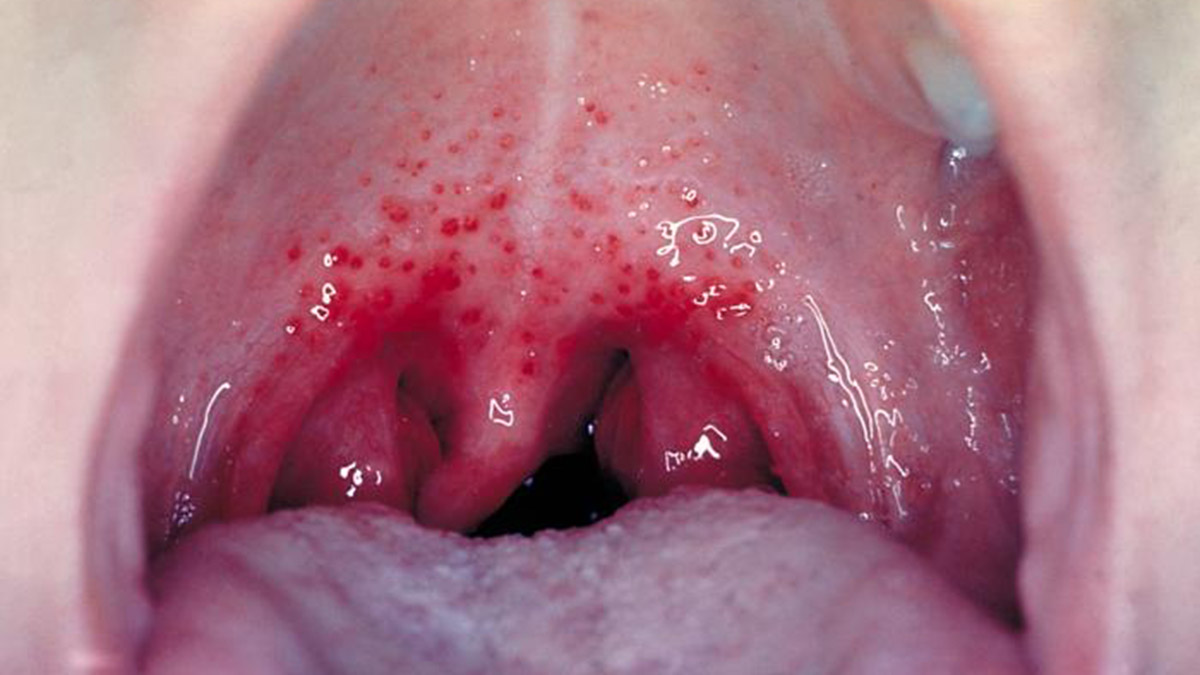

Vakaların çoğu nispeten hafif olsa da bazen Strep, vücudun savunmasını aşıp kan ve akciğerler gibi normalde bulunmadığı bölgelere bulaştığında yaşamı tehdit eden invaziv A Grubu Streptokok enfeksiyonuna (iGAS) neden olabileceği ifade edildi. Uzmanlar Strep A için erken belirtilerin yüksek ateş, boğazda şişmiş bezler, boğaz ağrısı, vücutta döküntü ve kas ağrıları olduğunu vurguladı.